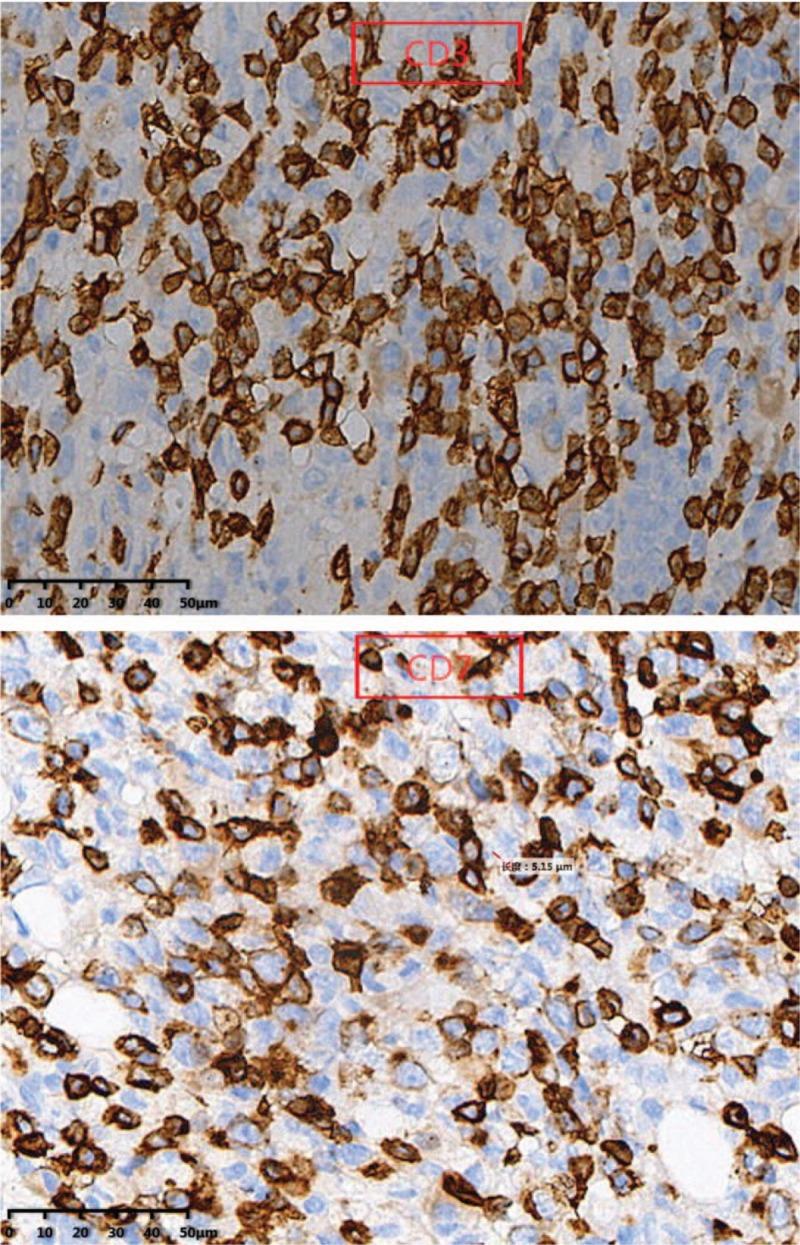

In immunophenotype analysis, CD2, CD3, CD7, and CD68 were positive and CD56 was suspiciously positive. Granzyme B and T-cell intracellular antigen (TIA-1) were also positive and in situ hybridization was positive for Epstein-Barr virus-encoded mRNA (EBER). Ki-67 was 60%+. Nuclide bone scan showed that the nuclide was unusually concentrated in the sixth thoracic vertebra which considered extremely active and slightly concentrated in the right sacrolilac joint. Magnetic resonance imaging detected an abnormal signal in the sixth thoracic vertebra with corresponding paravertebral and intraspinal occupying lesion. Based on the above features, a diagnosis of ENKTCL was made.

免疫表型分析中,CD2、CD3、CD7和CD68呈阳性,CD56可疑阳性。颗粒酶B和T细胞胞内抗原(TIA-1)也呈阳性,原位杂交检测到爱泼斯坦-巴尔病毒编码的mRNA(EBER)呈阳性。Ki-67为60%+。核素骨扫描显示核素异常浓聚于第六胸椎,提示该部位极度活跃,右侧骶髂关节有轻度浓聚。磁共振成像检测到第六胸椎有异常信号,伴有相应的椎旁及椎管内占位性病变。基于上述特征,诊断为ENKTCL。